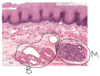

Small intestine - muscularis externa, intestinal glands, submucosa, muscularis mucosa, intestinal villi

Microvilli of the Duodenum - microvilli (curved arrows) of the duodenum. Each microvillus is covered with the plasma membrane which has an external glycocalyx of glycoproteins some of which function as enzymes that participate in the terminal digestion of proteins and carbohydrated. The central core of the microvilli is occupied by actin microfilaments and several actin binding proteins. Microfilaments from the microvilli extend into the apical cytoplasm to from part of the terminal web (TW).